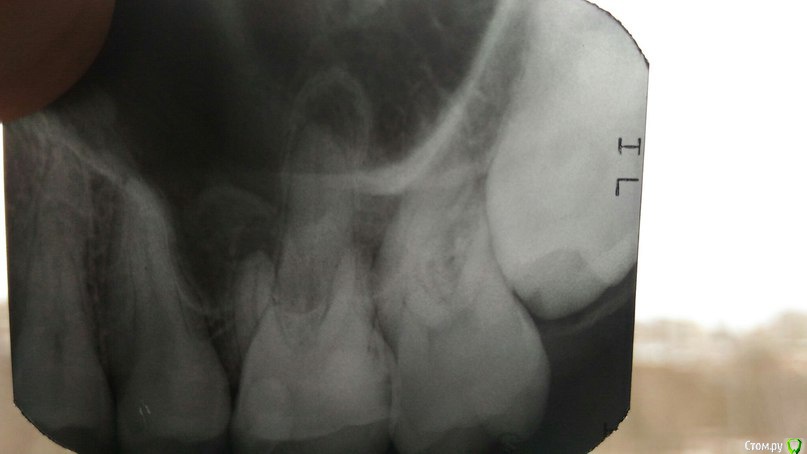

Дмитрий1990 Опубликовано 25 марта, 2016 Поделиться Опубликовано 25 марта, 2016 Здравствуйте! Сегодня нашел шишку у себя на десне над верхним зубом, сходил к врачу... она сказала что дело плохо, зуб надо удалять... отправила к другому врачу, что бы решил как лучше его удалить, но к нему я пойду только завтра. Там как я понял у меня загноились три корня и так просто его не удалишь могут быть последствия. Подскажите что лучше сделать и какие могут быть последствия. Благодарю! Ссылка на комментарий

___49___ Опубликовано 26 марта, 2016 Поделиться Опубликовано 26 марта, 2016 И 8ки удалите . Ссылка на комментарий